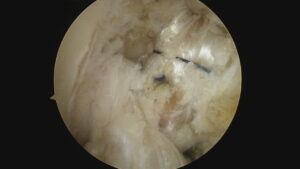

金属の棒で触れている部分が、後十字靭帯の付着部ですが、

剥がれてなくなっています。

2本見える靭帯のうち右側が再建靭帯です。

動画では再建靭帯の緊張が良好であることが確認できます。